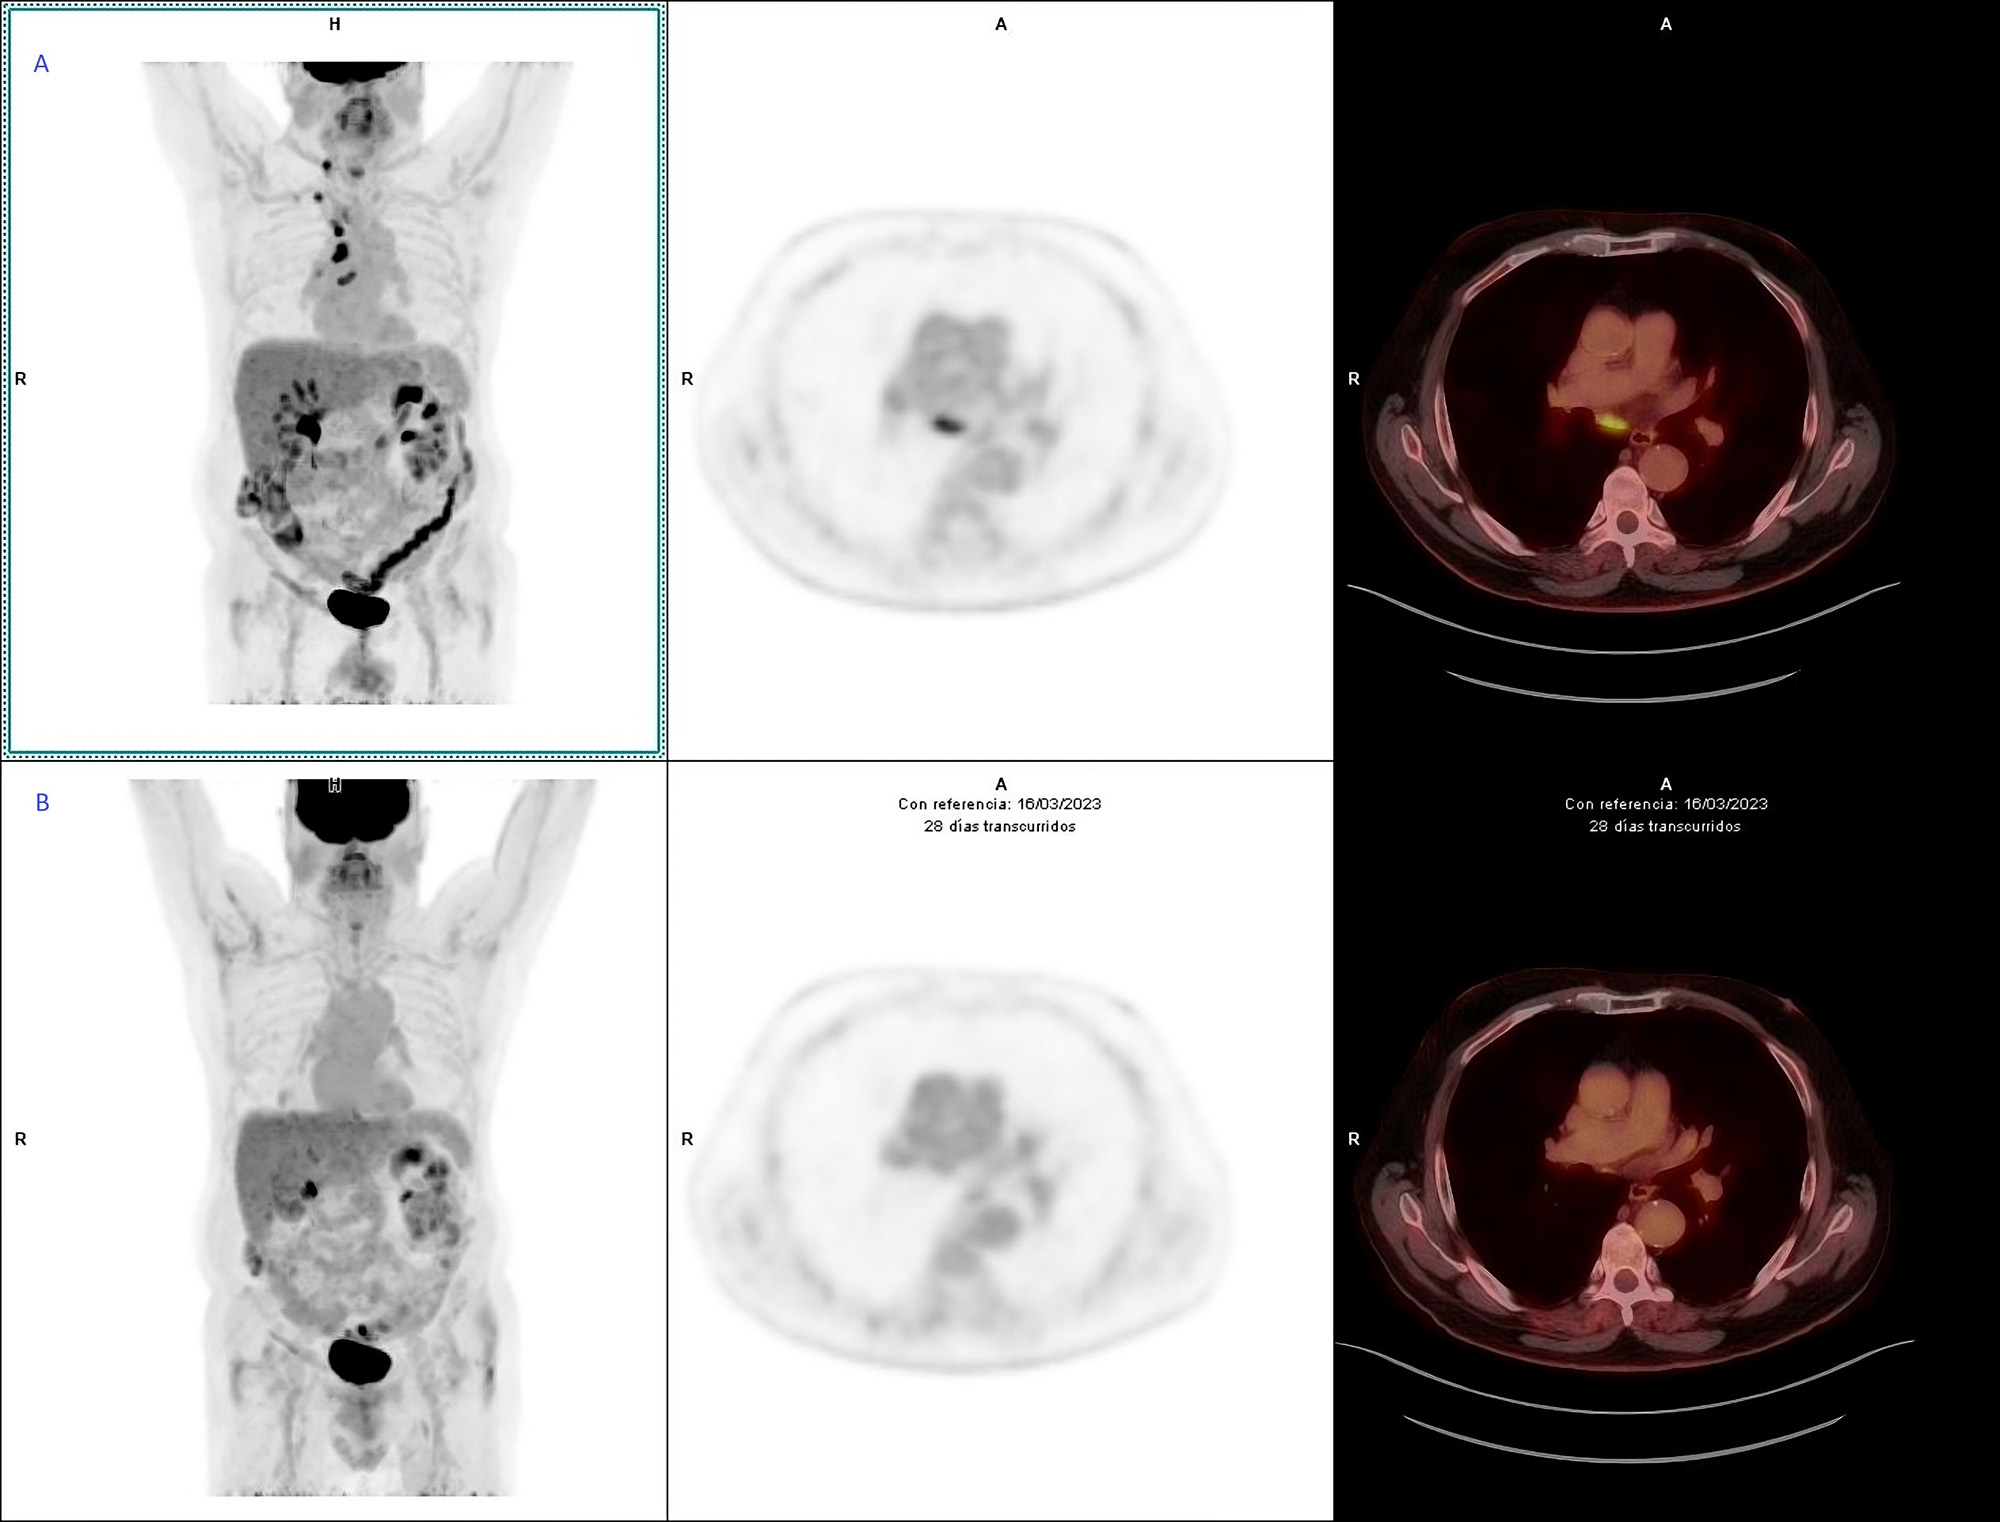

Varón de 74 años, exfumador, con antecedentes de cáncer de próstata tratado mediante radioterapia, ateromatosis generalizada, EPOC, osteoporosis y diverticulosis. En seguimiento por Medicina Interna por dolores óseos generalizados y artralgias, se solicitó PET/TC con 18F-FDG para descartar enfermedad metastásica, ante una resonancia magnética previa que mostraba fracturas vertebrales con edema. No se disponía de otros estudios de imagen recientes. El PET/TC evidenció adenopatías hipermetabólicas en compartimento yugulocarotídeo derecho, en sectores supraclavicular derecho y mediastínicos y un micronódulo pulmonar ametabólico en lóbulo medio (Fig.1.A). Se realizó análisis visual y semicuantitativo con cálculo de SUVmax de las adenopatías (Fig.2.A). Como hallazgos adicionales, se observó extensa calcificación coronaria, concordante con la ateromatosis generalizada del paciente, de interés para la valoración del riesgo cardiovascular. Asimismo, se objetivó aumento del metabolismo en el hemicolon izquierdo (SUVmax= 8,4), sugestivo de afectación inflamatoria, que posteriormente fue confirmada como sigmoiditis crónica en la colonoscopia con biopsia.

Se inició Pembrolizumab 200 mg cada 21 días. El PET/TC tras el primer ciclo mostró respuesta metabólica completa de la afectación ganglionar (Fig. 2 B), persistiendo el micronódulo pulmonar en lóbulo medio sin captación (Fig. 1 B).

Figura 2.B. Estudio de control tras el primer ciclo de tratamiento con Pembrolizumab: respuesta metabólica completa de las adenopatías previamente detectadas, sin aparición de nuevas lesiones hipermetabólicas.